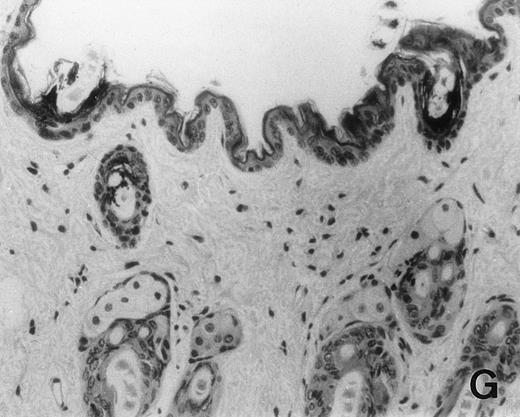

Previous in vitro studies showed that mdm100-specific, allo-restricted CTL killed H-2b tumor cells, including lymphoma cells, but not normal cells.24 However, only a limited selection of normal cells such as dendritic cells and Con-A–activated lymphocytes was available for in vitro tests. Thus, it remained unclear whether some normal tissues in vivo express sufficient levels of mdm-2 to trigger killing by the injected CTL. Several lines of evidence suggested that injected CTL did not attack normal host tissues. Firstly, none of the mice showed any acute side effects after CTL injection. Secondly, the recovery from BMT and the general health status were indistinguishable in mice that received CTL compared with control mice. Thirdly, histological analysis of liver, gut, and skin from 4 CTL treated and 4 untreated mice showed that these tissues, which are normally affected by GVHD, showed similar histology in mice with or without CTL administration (Fig 6). This indicated that CTL injection did not cause the tissue damage that is frequently seen in BMT individuals after infusion of allogeneic T lymphocytes.

Histology of BMT mice. (A through D) The histology of C57BL/6 mice transplanted with B10.A(4R) BM. One group of mice was injected with allo-restricted CTL while the control group did not receive CTL. (A) Liver from a CTL-treated mouse 3 weeks posttransplant, with no significant inflammation or necrosis. (B) Liver from a control mouse 3 weeks posttransplant, with mild periportal inflammation. Skin from a CTL-treated mouse (C) and a control mouse (D) 3 weeks posttransplant, with no significant inflammation or keratinocyte necrosis. Tissues were also examined at 4, 5, and 6 weeks posttransplant and showed no evidence of GVHD in either CTL-treated or control mice (not shown). (E-H) show the histology of (C57BL/6 × BALB/c) F1 mice, transplanted with BM from littermates. One group of mice was injected with allo-restricted CTL and a control group did not receive CTL. (E) Liver from a CTL-treated mouse 4 weeks posttransplant, with no significant inflammation or necrosis. (F) Liver from control mouse 4 weeks posttransplant, with no significant inflammation and necrosis. Skin from a CTL-treated mouse (G) and a control mouse (H) 4 weeks posttransplant, with no significant inflammation or keratinocyte necrosis. Tissues were also examined at 3 and 5 weeks posttransplant and showed no evidence of GVHD in either CTL-treated or control mice (not shown). (All H&E-stained sections, original magnification × 20.) Sections from colon and stomach also showed no significant inflammation (not shown).

We explored whether immune responses of BMT C57BL/6 hosts against BALB/c-derived CTL prevented the induction of GVHD by injected CTL. If this were the case, we predicted that CTL injection into (C57BL/6 × BALB/c) F1 hosts would result in GVHD. Thus, (C57BL/6 × BALB/c) F1 mice were transplanted with BM from littermates using the same conditioning protocol that was used for all experiments in this study. One group of transplanted mice was injected with 1.5 × 107 allo-restricted CTL and a control group did not receive any CTL. Histology of skin, liver, stomach, and gut performed after 3, 4, and 5 weeks showed that injected CTL did not cause GVHD in these F1 hosts (Fig 6E through H). Thus, lack of GVHD was not dependent on host immune responses against injected CTL.